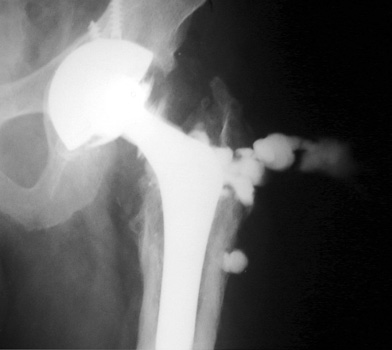

Arthrographic evidence of cup looseningcontrast enters

abnormally widened interface Gruen zone II and III